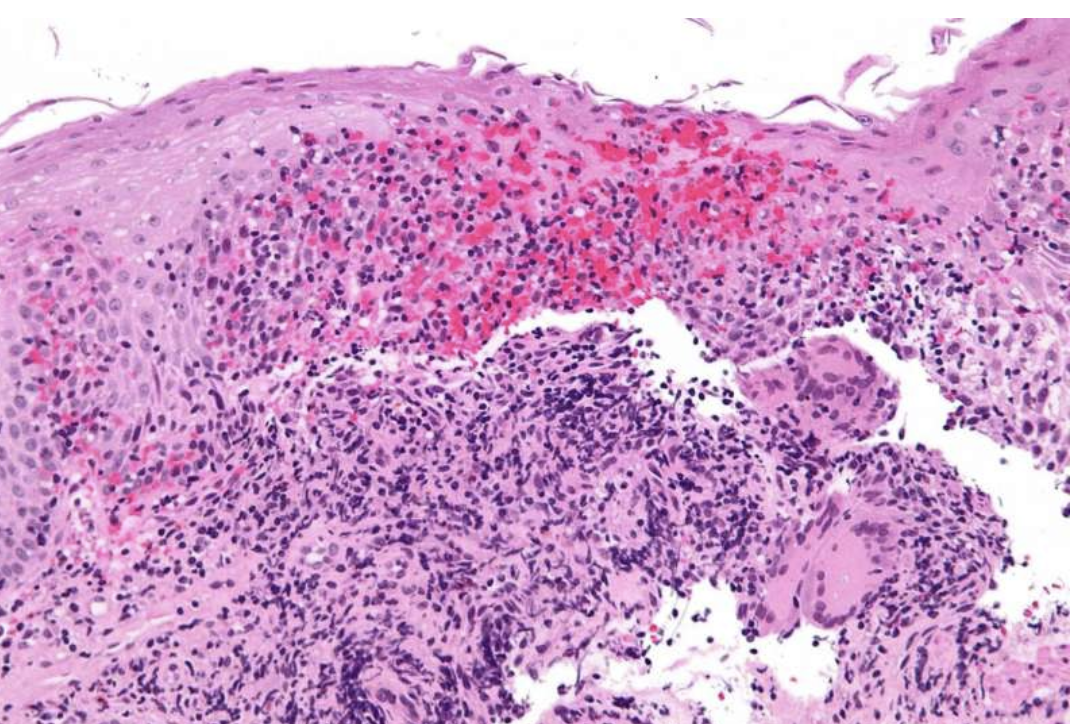

亲爱的朋友们,今天我想和大家聊聊一个让我既痛苦又不得不面对的话题——克罗恩病。这不仅仅是一种疾病,它几乎成了我生活中的一部分,时时刻刻提醒我它的存在。

治疗克罗恩病,就像是在进行一场没有硝烟的战争。每一次的药物调整,每一次的医疗检查,都是我对抗这场战争的策略。虽然过程充满了不确定和焦虑,但我始终相信,总有一天,我会找到属于我的胜利之路。